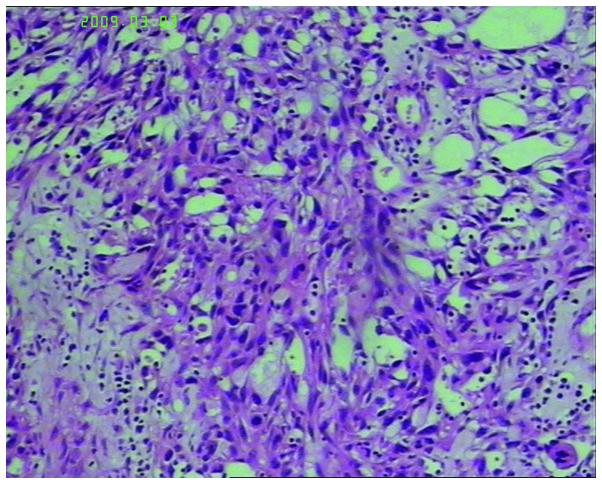

Angiosarcoma is a rare and deadly malignancy originating from the vascular endothelial cells. Surgery is the most effective method to cure this disease, but for metastatic angiosarcoma, a chemotherapy-based treatment is the main therapeutic choice. However, there is currently no standard chemotherapy regimen. The current study reports the case of a 66-year-old male with post-operative scalp angiosarcoma recurrence and multiple metastases. The patient obtained a complete response to first-line combination chemotherapy consisting of cyclophosphamide, epirubicin, vincristine and dacarbazine, with a progression-free survival time of eight months. After benefitting from subsequent comprehensive treatment including, cyclophosphamide, epirubicin, vincristine, dacarbazine, docetaxel, cisplatin, gemcitabine and radiotherapy and anti-angiogenic therapy, the patient obtained an overall survival time of 38 months following initial diagnosis.

血管肉瘤是一种起源于血管内皮细胞的罕见且致命的恶性肿瘤。手术是治愈这种疾病最有效的方法,但对于转移性血管肉瘤,以化疗为主的治疗是主要的治疗选择。然而,目前尚无标准的化疗方案。本研究报告了一例66岁男性,术后头皮血管肉瘤复发并多发转移。该患者对由环磷酰胺、表柔比星、长春新碱和达卡巴嗪组成的一线联合化疗获得完全缓解,无进展生存期为8个月。在受益于包括环磷酰胺、表柔比星、长春新碱、达卡巴嗪、多西他赛、顺铂、吉西他滨以及放疗和抗血管生成治疗在内的后续综合治疗后,该患者自初次诊断后获得了38个月的总生存期。